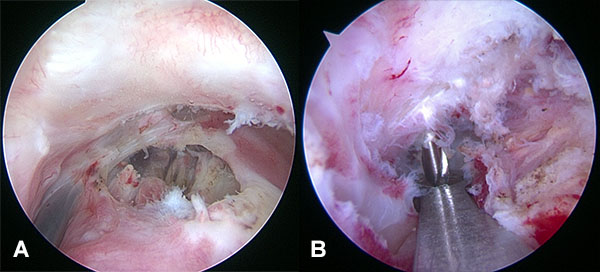

Con el paciente con bloqueo interescalénico y en posición de silla de playa con el brazo sin tracción en 10 a 20 grados de flexión y 20 a 30 grados de abducción, se introduce artroscopio por un portal posterior estándar y se realiza una artroscopia diagnostica en busca de lesiones asociadas. Se realiza un portal antero-inferior justo por encima del tendón del subescapular levemente más lateral de lo convencional con técnica de afuera-adentro y con dirección a la base de la coracoides, se realiza la colocación de cánula de 8,25 mm. Se realiza la apertura del intervalo de los rotador con shaver y electro bisturí artroscópico hasta la visualización de la punta y la base de la coracoides. Luego realizamos un nuevo portal percutáneo anterosuperolateral con técnica de afuera adentro y lo establecemos como nuevo portal de visión. Completamos la exposición de la base de la coracoides en la unión con la cara anterior del omoplato (fig. 1A) Se introduce el compás guía para AC TightRope o sistema DogBone por el portal antero inferior y se lo posiciona centrado en la coracoides a nivel de la unión de la base de la coracoides con la cara anterior del omoplato en 70 a 90 grados de angulación (fig. 1B). Se realiza un abordaje longitudinal de 2 a 3 cm a nivel del foco de fractura, se limpia foco de fractura, se reseca tejido interpuesto y se realiza la reducción de la fractura y fijación transitoria con clavijas de 1,6 mm, se controla reducción por radioscopia (fig. 2). La guía del compas es posicionada entre 25 y 30 mm medial a la articulación acromioclavicular y centrada en la clavícula para evitar lesionar la cortical anterior o posterior. Se realiza la perforación de la clavícula y la coracoides con drill pin canulado de 3 mm atravesando 4 corticales para pasar a través de la clavícula y coracoides visualizando posicionamiento por radioscopia, y control por artroscopia de la salida del drill pin en la base de la coracoides, se retira el pin del drill canulado y se introduce un alambre de nitinol que se recupera por el portal antero inferior (fig 3). Se retira el drill canulado dejando el alambre de nitinol. Si vamos a utilizar sistema AC TightRope debemos desmontar ambos botones del FiberWire y montar dos suturas FiberTape en el botón longitudinal para pasar a través del túnel coracoideo y clavicular solo los cuatro extremos suturas. Se montan los 4 extremos de las suturas FiberTape del implante subcoracoideo en el alambre de nitinol y se realiza el pasaje del mismo de distal a proximal (fig. 4). Bajo visión artroscópica directa se comprueba el pasaje y posicionamiento del botón subcoracoideo (fig. 5). Se realiza la reducción de la fractura aplicando presión inferior sobre el fragmento proximal de la fractura y contrapresión superior desde el codo para ayudar a reducir la fractura. Una vez reducida la fractura bajo control radioscópico se completa la fijación del botón clavicular del sistema AC TightRope o DogBone y con sutura FiberTape transósea se incorpora el fragmento distal de la fractura a la reconstrucción (fig. 6).

Figura 1: Guía de posicionamiento AC TightRope Subcoracoidea en la unión de la Base de la coracoides con la cara anterior del omoplato.